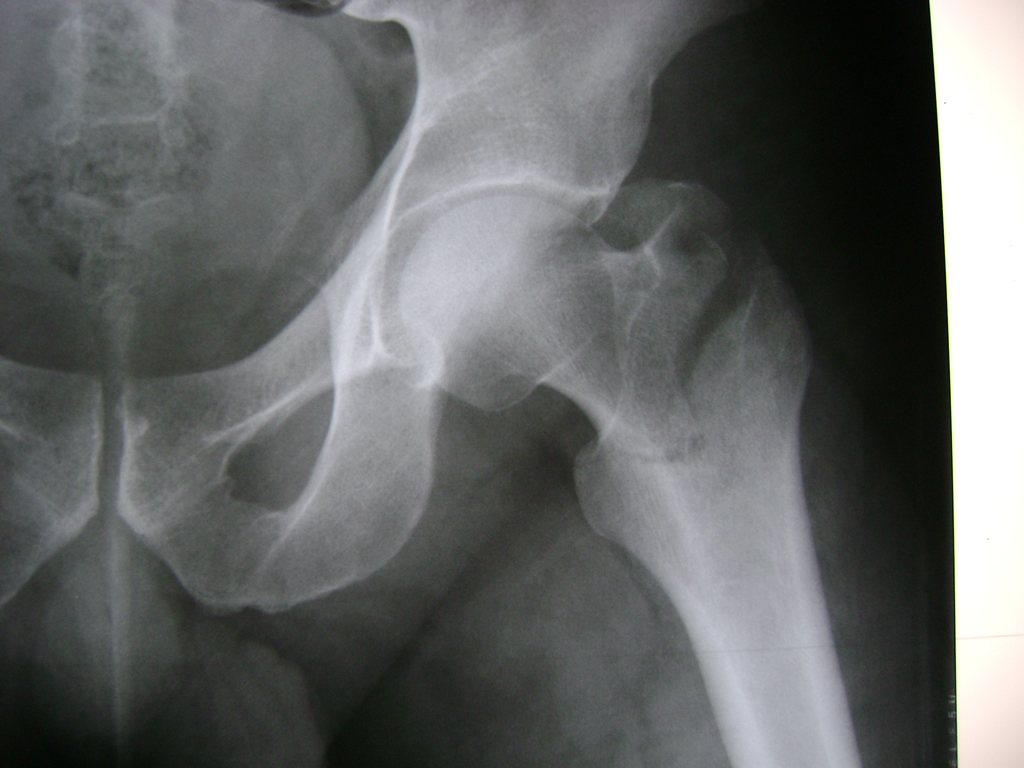

Fémur - Cadera

La cirugía de fractura de cadera se realiza para reparar una ruptura en la parte superior del hueso del muslo. Este hueso se denomina fémur.

Es parte de la articulación coxofemoral. Si una fractura de cadera no recibe tratamiento, es posible que deba permanecer en una silla o en la cama.